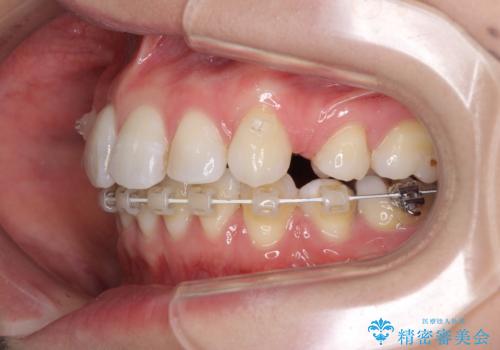

- ハーフリンガル

目立たない装置を希望されたので、上顎が裏側装置のハーフリンガルを選択し、上下左右の小臼歯(計4歯)を抜歯して矯正治療を行うこととしました。

治療期間の目安は3年~3年半でしたが、咬み合わせにより上顎のスペースがなかかな閉じきらず、治療期間が長期化してしまいました。